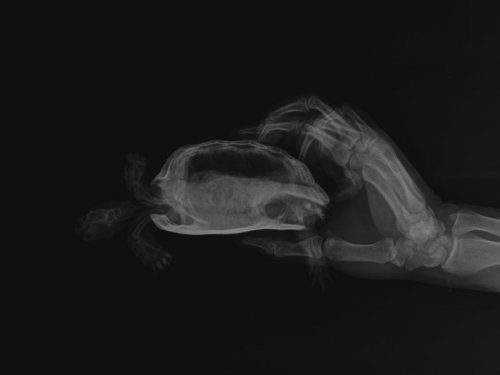

Podolnyi Ваше имя: Подольный Константин Локация: Украина, Днепр Опубликовано: 7 октября 2020 Опубликовано: 7 октября 2020 У всех трёх, согласно рентгену - нарушена минерализация костных структур. У первой черепахи это видно в поясничном отделе позвоночника (идёт позвоночник с четкой картинкой и после размывается), у второй черепахи весь позвоночный стол уже затронут. третья черепах, более интересный пациент. У неё также затронут весь позвоночный столб и ко всему-же был перелом позвоночника. Был он, скорее всего, за счёт метаболических нарушений. По поводу «клапанов», нет у рептилий никаких клапанов. У черепахи есть патология дыхательной системы: на легочном поле есть выраженный фиброзный процесс с образованием отдельных полостей, которые все же участвуют в акте дыхания. клиника дыхательной недостаточности есть ? Ей можно сдать общий анализ крови. И всем черепахам пройти курс элеовита и кальция глюконата. И на будущее 2 раза в год это делать. Кормить их раз в 3 дня, на 30 минут ставите еду и сколько съедят - после убираете остаток. Иногда, пропускать 1 кормление, т.е. раз в 6 дней кормёжка.

victoria146 Ваше имя: Виктория Локация: Воронеж Опубликовано: 11 октября 2020 Автор Опубликовано: 11 октября 2020 @moth это важное уточнение, спасибо! Так эти травы будут полезны? Хотелось бы у спецов узнать про магний. Как часто можно добавлять кальций+магний, потому как Аркадия заявляет что согласно последним исследованиям магний очень важен для рептилий.